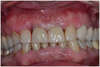

L’empreinte est réalisée et la prothèse sera posée le soir même.

Il s’agit d’une restauration FIXE